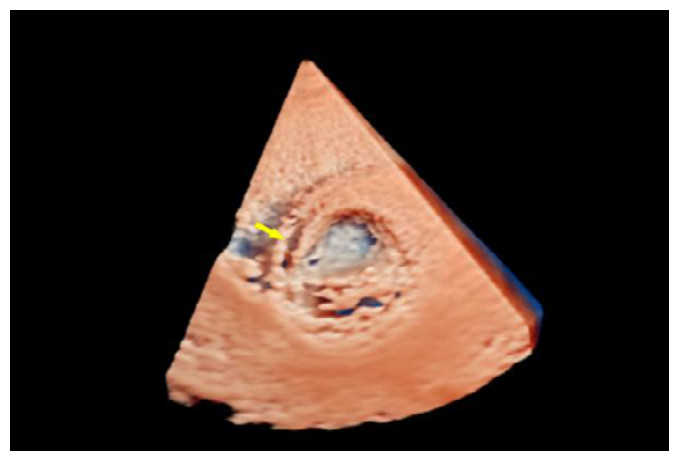

辅助检查如下。实验室检查:高敏C反应蛋白(hs-CRP)和红细胞沉降率(erythrocyte sedimentation rate, ESR)轻度升高。心电图:正常窦性心律,无ST段异常改变。胸部CT:双侧肺门中心对称分布的斑片状高密度影,部分实变,伴空气支气管征,病变边缘模糊。超声心动图:二维超声(2D)主动脉短轴切面显示右乏氏窦瘤破裂(ruptured of ASV, RASV),破入右心房形成“囊袋状”结构,长约1.7 cm,基底部破口内径约0.8 cm(图 1A)。彩色多普勒(color Doppler flow imaging, CDFI)显示全心动周期的左向右分流(图 1B)。连续多普勒(continuous doppler, CW)测得连续分流。室间隔内见4.0 cm×0.7 cm无回声区(图 2A),CDFI显示彩色血流信号随心动周期进出该无回声区(图 2B),考虑室间隔夹层瘤(dissecting aneurysm of the interventricular septum, DAIS)。实时双平面成像同步显示窦瘤破口与室间隔夹层相延续。应用Philips TrueVue三维(three-dimensional, 3D)超声心动图成像模式直观展示室间隔夹层瘤的立体结构(图 3)。

| 图 3 3D超声显示左室短轴切面室间隔夹层动脉瘤立体结构 |